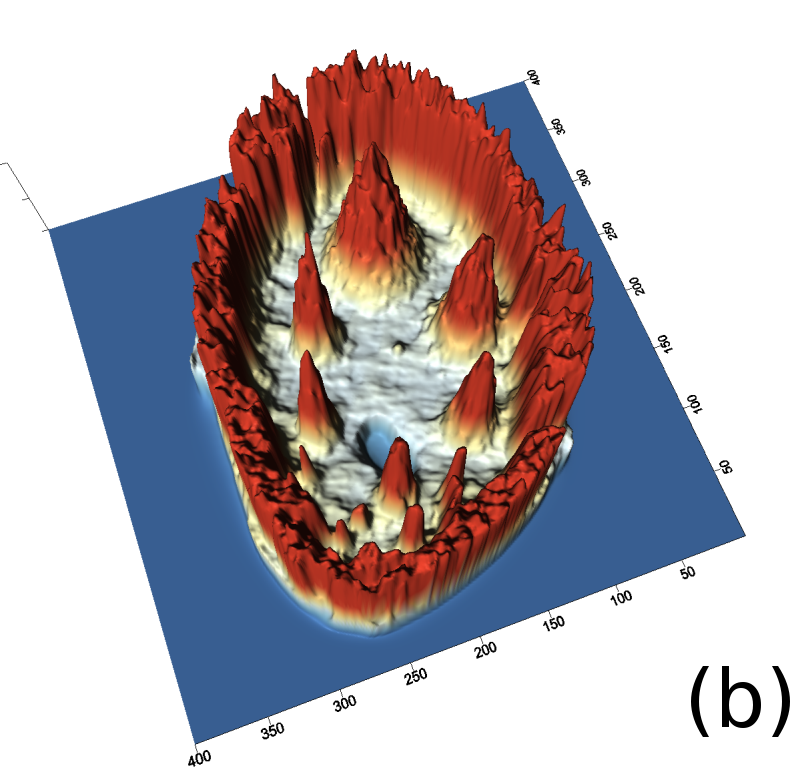

Reconstructed images are presented in Fig. 4. Since CGLS-TV- reconstruction might look more appealing than CGLS-EL we also show the surface representations of reconstructed images (see Fig. 5) and horizontal middle cross-sections (see Fig. 6).

One can notice that CGLS reconstruction is very noisy. CGLS-TV method better suppresses noise, however smooth features are strongly affected by the “staircasing” effect. CGLS-TV- method provides reconstruction with smoother features and CGLS-EL method resolves smooth features even better (e.g. cone-shaped parabola). Although CGLS-EL method performs very well for smooth objects one can notice the wave-like variations of intensity in the background and also at the top of the rectangle (see Fig. 6). This issue can be explained by the properties of our regularizer, in contrast to TV, our penalty does not seek the sparsest solution and does not penalize strongly (pushing to the constant value) a small intensity perturbations. The EL term tends to preserve all sharp edges while uniform noise is smoothed isotropically with the Laplacian. In Fig. 6 one can see that the CGLS-EL method provides better recovery of smooth features while slightly higher (compare to TV and TV-) perturbations visible in uniform areas (the top of the rectangle), however, the edges of the rectangle are defined sharper with the EL penalty.

In Fig. 10 and 11 one can notice that the BR is very smooth for TV and TV- penalties and some long-wave oscillations can be seen in the reconstructed image with EL penalty. This result corresponds to the expected behaviour of the EL penalty. We note here that the phantoms background (see Fig. 7) is not as flat as TV and TV- penalty recovered it. Furthermore, a small size dot-like feature (approximately in the centre of the phantom) is almost smoothed out with TV and TV- recovery. However, it is visible and well recovered with EL penalty. The sharp features, overall, are reconstructed very well with MLEM-EL method and seem even sharper compare to other methods (see the bone outer rim in Fig 10).